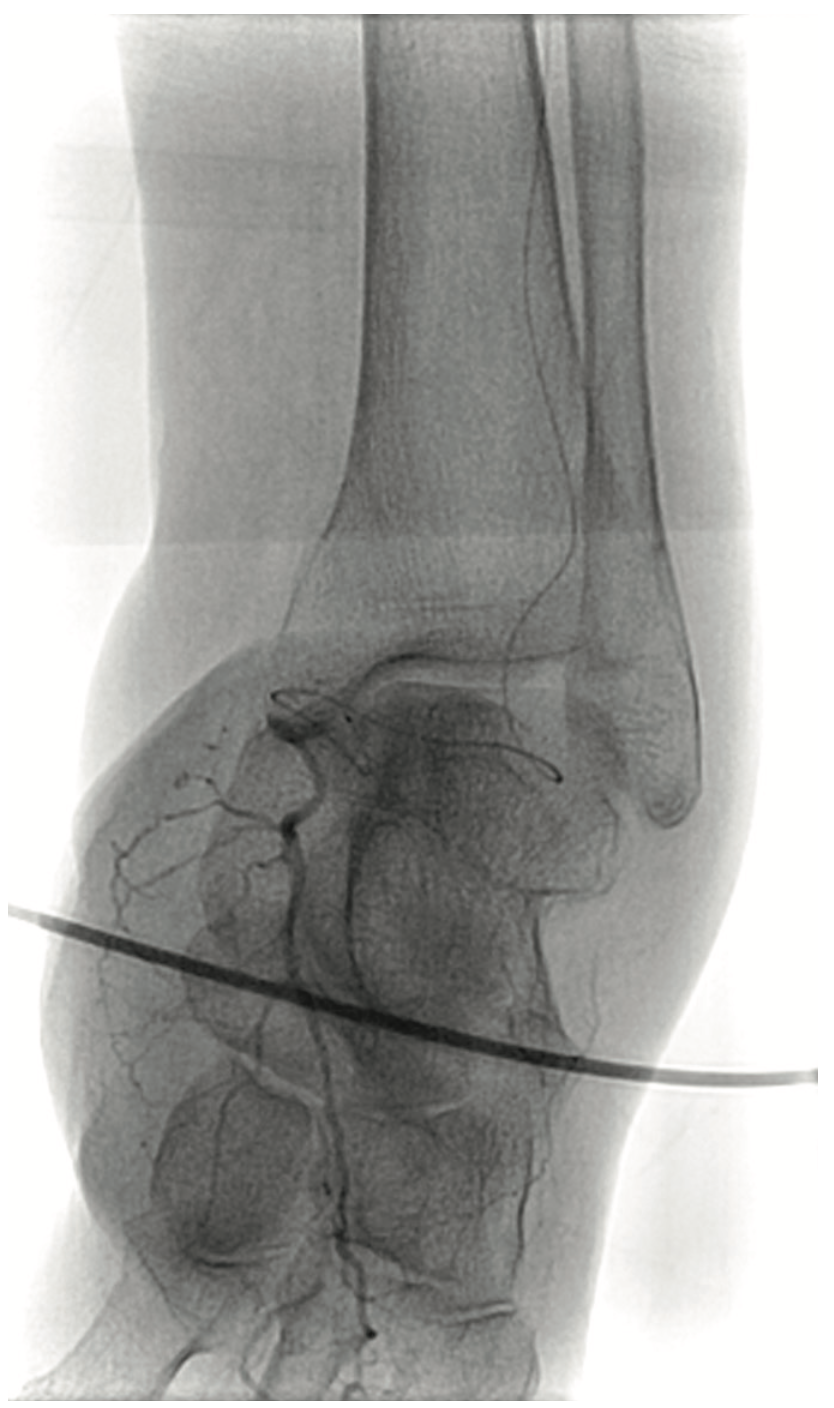

A 90-year-old woman presented with CLI of her left foot. She suffered from claudication beginning 12 years ago. Six months prior, she developed an ulcer on her foot and shortly thereafter, underwent femoral popliteal bypass. Her symptoms recurred and repeat fem-pop surgery was performed at that time. It immediately failed and she had a cadaveric vein placed as a fem-pop conduit, which again occluded and after two revisions of the fem-pop bypass, she was told five months prior to her current presentation that she would not be able to have any further intervention on her leg. At that time, it was suggested she go to hospice. A medial 1 cm x 6 cm foot ulcer was noted on examination, but the patient refused any intervention. Six weeks later, with insistence from the wound care center, and with the patient’s second and third digit now black on that foot, the patient permitted an evaluation for possible limb salvage. The examination showed that the foot was now cool and the second, third, and fourth digits were bluish-black. No pedal pulses were present. The patient was approached via the contralateral groin, and the angiogram revealed her native SFA and graft to be occluded at the origin (Figure 8). With the thought that there was a likelihood of thrombus in the vessel, we utilized the CrossLock LP and crossed the occlusion down to the tibial vessels with a Command wire (Abbott Vascular) wire (Figures 9-10). With some suggestion of thrombus in the digital arteries, 3 mg of tPA was administered locally. A .9 laser was used and subsequent balloon angioplasty was performed using embolic protection (Figures 11-12). The fluoroscopic time was 25.2 minutes and contrast was 273 cc. At the end of the procedure, the patient had 2-vessel infrapopliteal flow and several hours later, was seen by the orthopedic surgeon for metatarsal surgery. The surgeon stated that all the toes were now pink, the patient had palpable pedal pulses, and although it was very likely that some amount of amputation may be necessary in the second and third toe, nothing was removed, and the patient was discharged the next day.